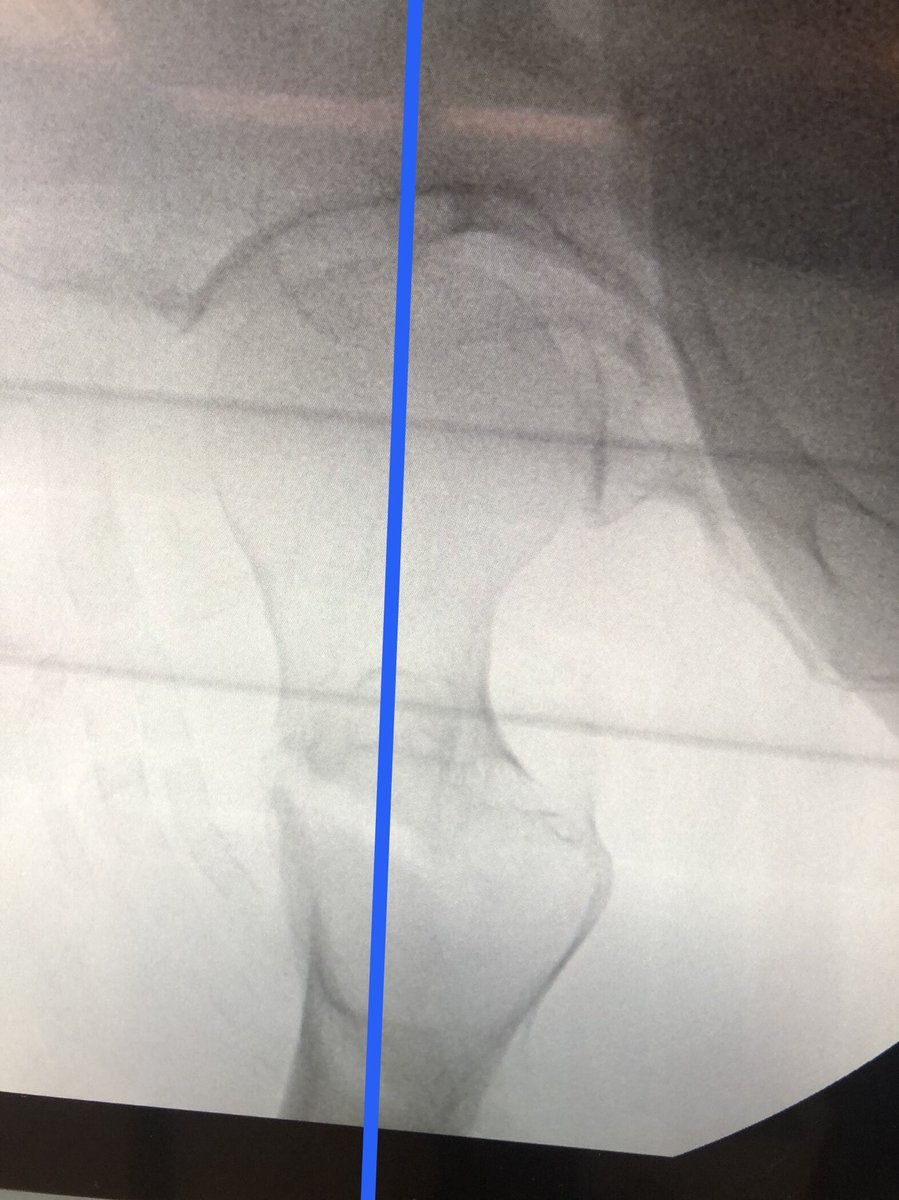

[4/18] The correct amount of traction, if you don’t want to judge by the other side, is usually close when greater trochanter lines up w/center of femoral head (yellow). You can play around with it and see how it looks. Can also always clamp if traction alone isn’t good enough.

[12/18] To see head well, the c-arm has to be sufficiently “wagged” proximally (yellow). Usually that solves most of my problems with lateral. My angle is about 75 deg from vertical in the other plane, to make up for the usual 15 degrees of anteversion (not quite a full lateral).

[13/18] When drilling/inserting screw, I usually do it on fluoro, I don’t just rely on the stopping point of sleeves because sometimes you can drive guidewire into pelvis. Also wire can come back out with drill so you need to be ready with obturator or another wire to stop it.